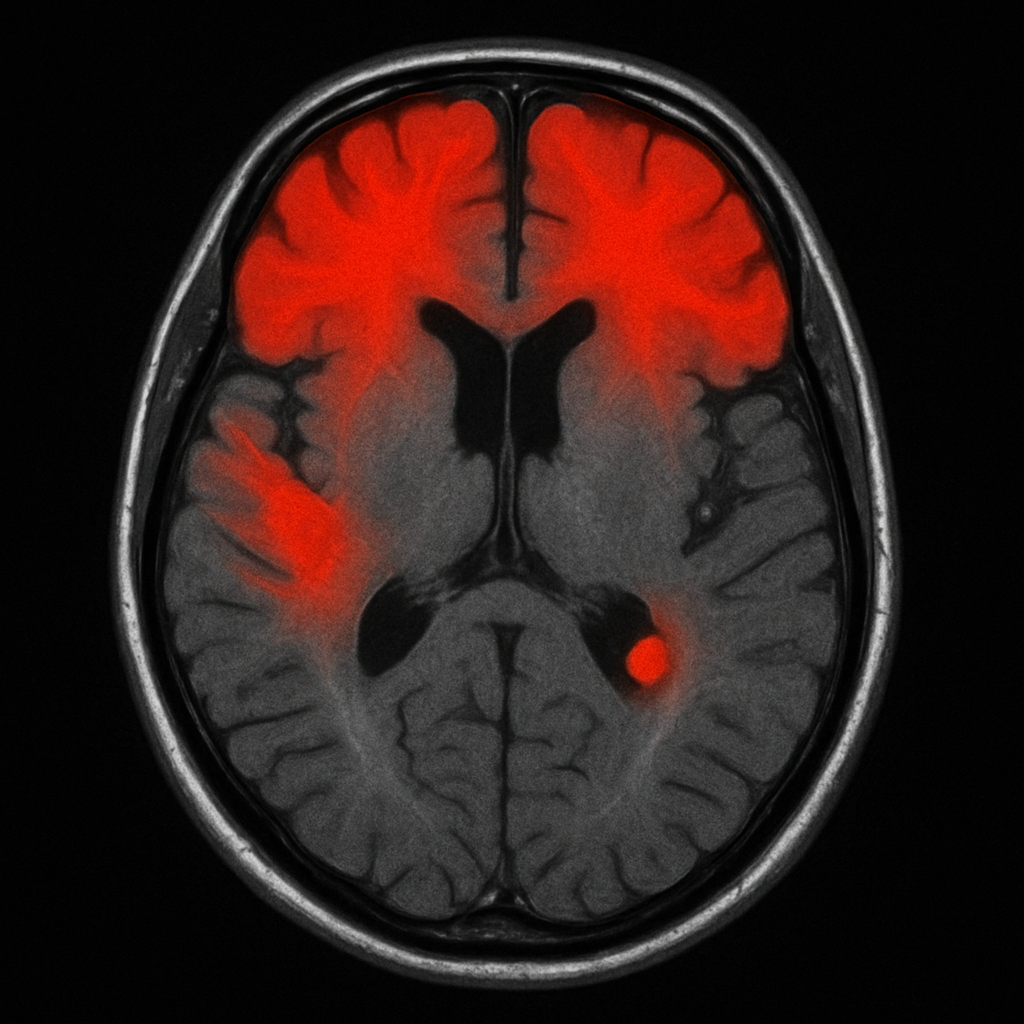

Researchers in Germany used artificial‑intelligence (AI) software to scan the brains of people who had recovered from COVID‑19. Here are the big take‑away.

* The most affected regions were the thinking‑and‑planning frontal lobe, the sensory‑processing parietal lobe, and a relay hub called the right thalamus. PubMed

More severe illness = more brain shrinkage.

The changes were still there months after recovery, even for patients who were never in intensive care.

Brain shrinkage in these areas can be linked to problems with memory, focus, and mood. PubMed